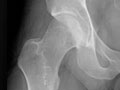

An extremity X-ray is a picture of your hand, wrist, arm, foot, ankle, knee, hip, or leg. It is done to see whether a bone has been fractured or a joint dislocated. It is also used to check for an injury or damage from conditions such as an infection, arthritis, bone growths (tumours), or other bone diseases, such as osteoporosis.

Extremity X-rays are done to:

• Find the cause of pain in an extremity.

• See if your bone is fractured or your joint is dislocated.

• See if fluid has built up in the joint or around a bone.

• See if your bones are positioned properly after treatment for a fracture or dislocation, such as after placing a cast or splint on an arm or leg. An X-ray also may be done after a doctor places a device such as a pin or an artificial joint in a bone.

• Find changes in your bones caused by conditions such as an infection, arthritis, bone growths (tumours), osteoarthritis of the hip, osteoarthritis of the knee, or other bone diseases.

• Find foreign objects such as pieces of glass or metal.

• Check to see if a child's bones are growing normally.

• See if your bones and joints are in the correct position after joint replacement surgery.